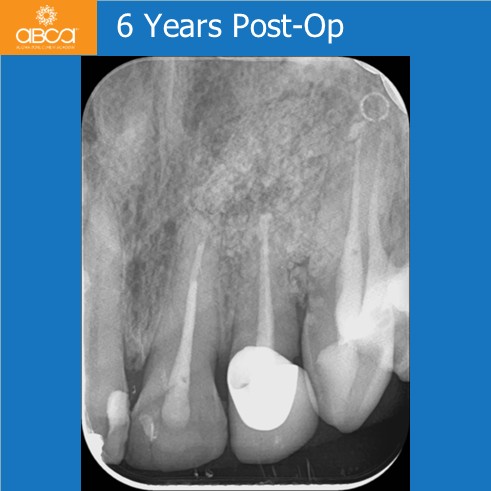

At the six-year follow-up, we observed good bone remodeling and healing, including complete and stable regeneration of both cortical plates.